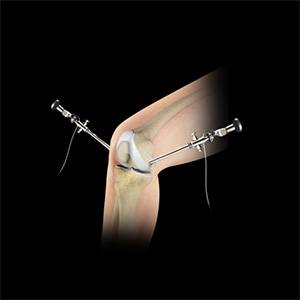

Knee Arthroscopy

Knee arthroscopy is a common surgical procedure performed using an arthroscope, a viewing instrument, to diagnose or treat a knee problem. It is a relatively safe procedure and you will usually be discharged from the hospital on the same day of surgery.